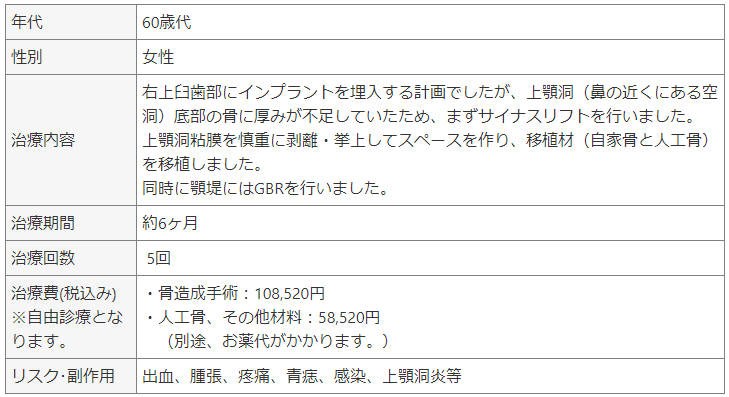

症例② サイナスリフト(上顎洞底挙上術)とGBR(骨誘導再生法)を行なった治療例。